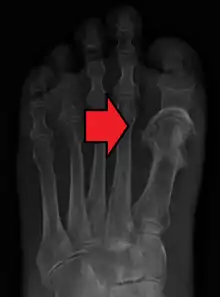

Fat embolism most commonly occurs as a result of fractures of bones such as the femur or pelvis.[3][1] Other potential causes include pancreatitis, orthopedic surgery, bone marrow transplant, and liposuction.[3][2] The underlying mechanism involves widespread inflammation.[3] Diagnosis is based on symptoms.[2]

Orthopaedic injuries especially fractures of the long bones are the most common cause of fat embolism syndrome (FES). The rates of fat embolism in long bone fractures vary from 1% to 30%. The mortality rate of fat-embolism syndrome is approximately 10–20%.[7] However, fat globules have been detected in 67% of those with orthopaedic trauma and can reach as high as 95% if the blood is sampled near the fracture site. As the early operative fixation of long bone fractures became a common practice, the incidence of FES has been reduced to between 0.9% and 11%.[6]